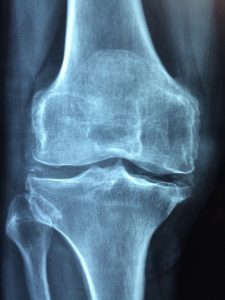

Røntgenundersøgelse

07 March 2023